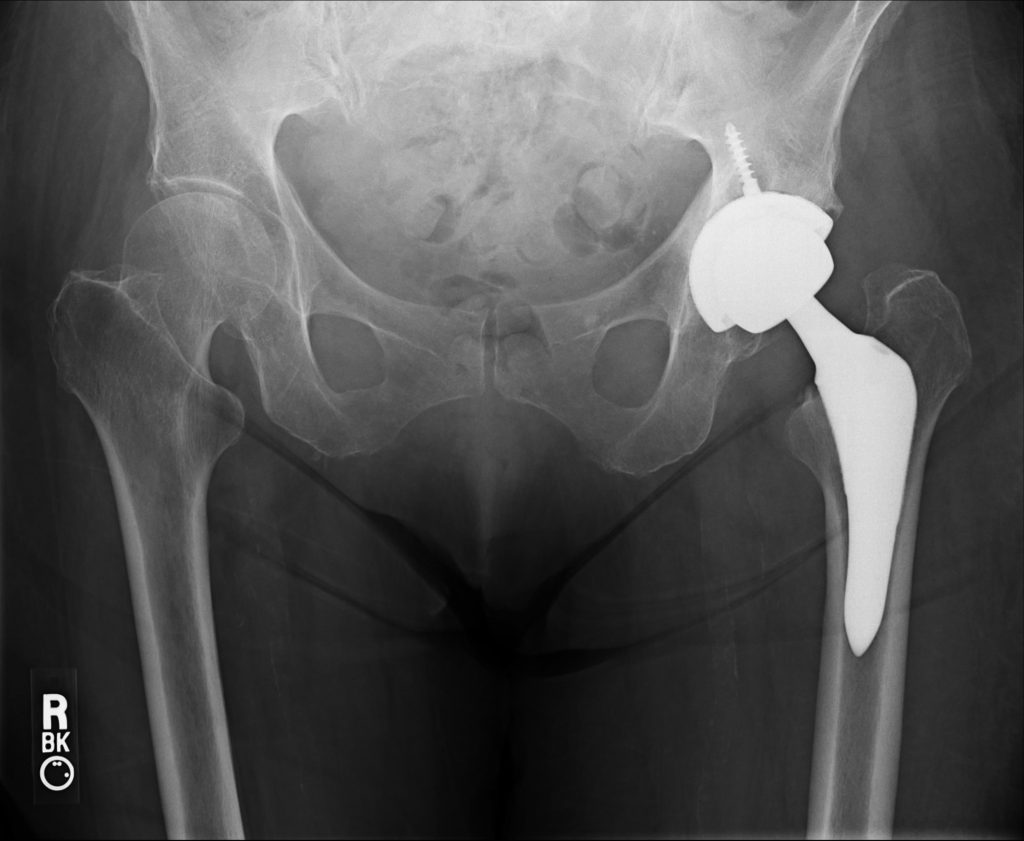

There are a few different methods and approaches when performing a total hip replacement. Much of the differences lie in the manner in which the hip joint is accessed. Generally speaking, the three approaches are the anterior, anterior-lateral, and posterior approaches. Although more technically demanding, the direct anterior approach is chosen by Dr. Lee for several reasons. For example, in a direct anterior approach, the muscles around the hip are merely moved out of the way during the surgery. No glute tendons are cut as with a posterior approach. Hip retractors are carefully placed to provide adequate visualization. As a result, no subsequent tendon repair is required, thus, alleviating the need for protecting a repair.

With a posterior approach, tendons around the hip must be cut and pulled out of the way in order to access the joint. These tendons are subsequently repaired but require several months of rehabilitation and healing time. Also, the posterior capsule of the hip joint must be opened to access the hip which puts the patient at increased risk for posterior hip dislocations. Therefore, after a posterior total hip, the patient requires several range of motion limitations including avoidance of deep hip flexion and crossing your legs. Therapy is also required to strengthen the surrounding muscles which can take around 3 months before the hip precautions are removed.